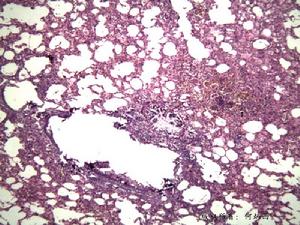

肝穿刺活組織檢查:顯示肝硬化PAS染色可見肝細胞內特徵性包涵體螢光染色顯示在肝細胞內蓄積有藍色顆粒即α1-抗胰蛋白酶抗體螢光帶

Α1抗胰蛋白酶缺乏性肝病尚不清楚為何一些人發生嚴重的肝病,而另一些人卻無症狀。多認為肝損害是由多方面因素引起的。如彈性蛋白酶能分解彈力纖維造成肺氣腫病變。但在正常情況下,彈性蛋白酶抑制因子可抑制此酶的活力,避免肺氣腫。研究發現PiZ較易發生慢性阻塞性肺疾病(COPD)。先天性α1-AT缺乏具遺傳易感性,需與後天外界因素結合才會產生致病作用。吸菸具有更大的危險性,如吸菸者肺巨噬細胞增多,細胞溶酶體多而大,菸草燃燒產生的NO2可刺激肺內巨噬細胞及中性粒細胞釋放彈性蛋白酶,而α1-AT缺乏者由於抑制蛋白酶的能力減弱,易發生肺組織損傷,從而引起慢性阻塞性肺疾病。α1-AT缺乏發生肝硬化者與肺部疾病無關。α1-AT缺乏是α1-AT缺乏性肝病的主要因素,還有其他因素參與,體內蛋白酶活性增高,是肝臟對其他一些致病因素和有毒物質的易感性增加,致使肝損害。Gam提出也有可能由於腸屏障破壞或有缺陷,腸內的毒素被吸收入肝,由肝Kupffer細胞攝取釋放出溶酶體酶,當人體缺乏α1-AT時該酶具有破壞性;或由於肝細胞內α1-AT滯留,腸毒素進入肝臟後,肝細胞內具有保護作用的蛋白溶解酶被過多的α1-AT抑制而使肝細胞受損;或因肝細胞內α1-AT過多而抑制了肝臟內源性蛋白酶的產生,以至不能對抗腸源性有毒物質,從而引起肝臟的損害。病理組織學改變因患者年齡而異。患病嬰兒的肝活標本檢查顯示膽管缺乏(bileductpaucity),肝細胞內膽汁淤積,伴有或不伴有細胞腫大變形,輕度炎性改變或脂肪變。肝細胞內可見一些特徵性的PAS陽性的耐澱粉酶樣小體(diastaseresistantglobule)。這種小體能被螢光素標記的α1-AT抗血清強烈染色,具有α1-AT抗原性。這種顆粒狀的包涵物位於肝細胞內質網上,隨著年齡的增長而增多。說明患者α1-AT的缺乏是由於合成的α1-AT不能釋放入血而蓄積於肝細胞內。以純合子PiZZ表現型患者為多。嬰兒期α1-AT缺乏的肝病患者,如無好轉可發生進行性肝損害。在門靜脈區纖維組織明顯增生,逐漸形成小葉間纖維化,可進一步呈小結節型或大結節型肝硬化。合子型α1-AT缺乏可引發原發性肝癌。

2.pi表型分析套用等電聚焦或酸性條件下瓊脂電泳鑑定α1-抗胰蛋白酶表型可建立診斷。目前,PCR技術已用於檢測α1-抗胰蛋白酶變異體,此法不僅迅速、敏感性高,而且只需極少量的細胞物質,該技術對確定診斷、人群篩檢及出生前診斷等均有用。肝穿刺活組織檢查:顯示肝硬化,PAS染色可見肝細胞內特徵性包涵體,螢光染色顯示在肝細胞內蓄積有藍色顆粒,即α1-抗胰蛋白酶抗體螢光帶。